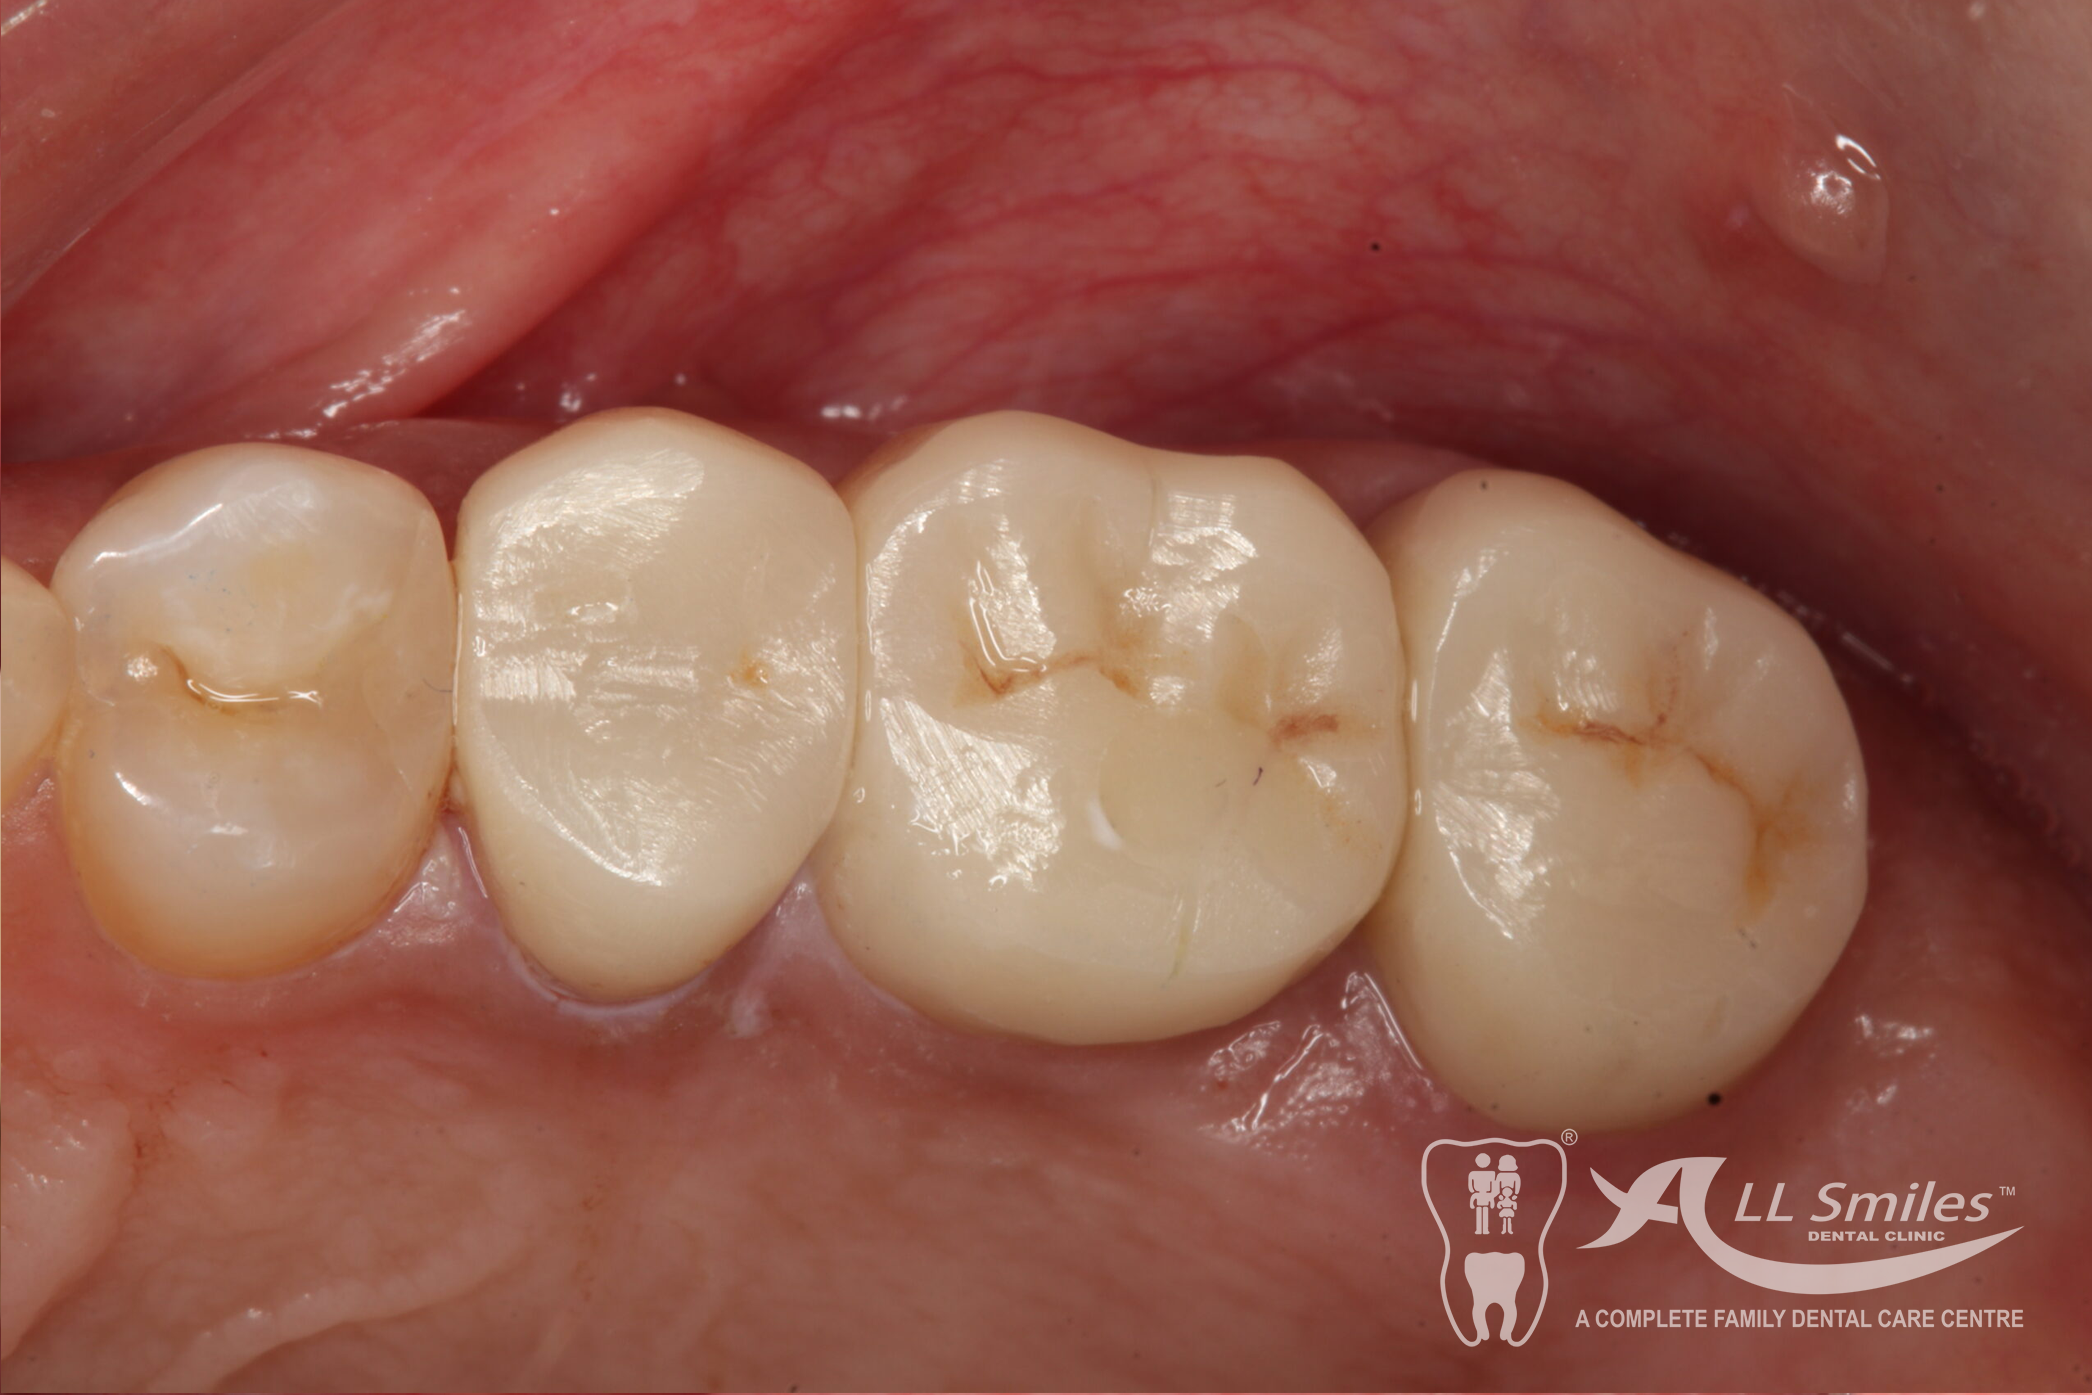

Dental Implants Gallery